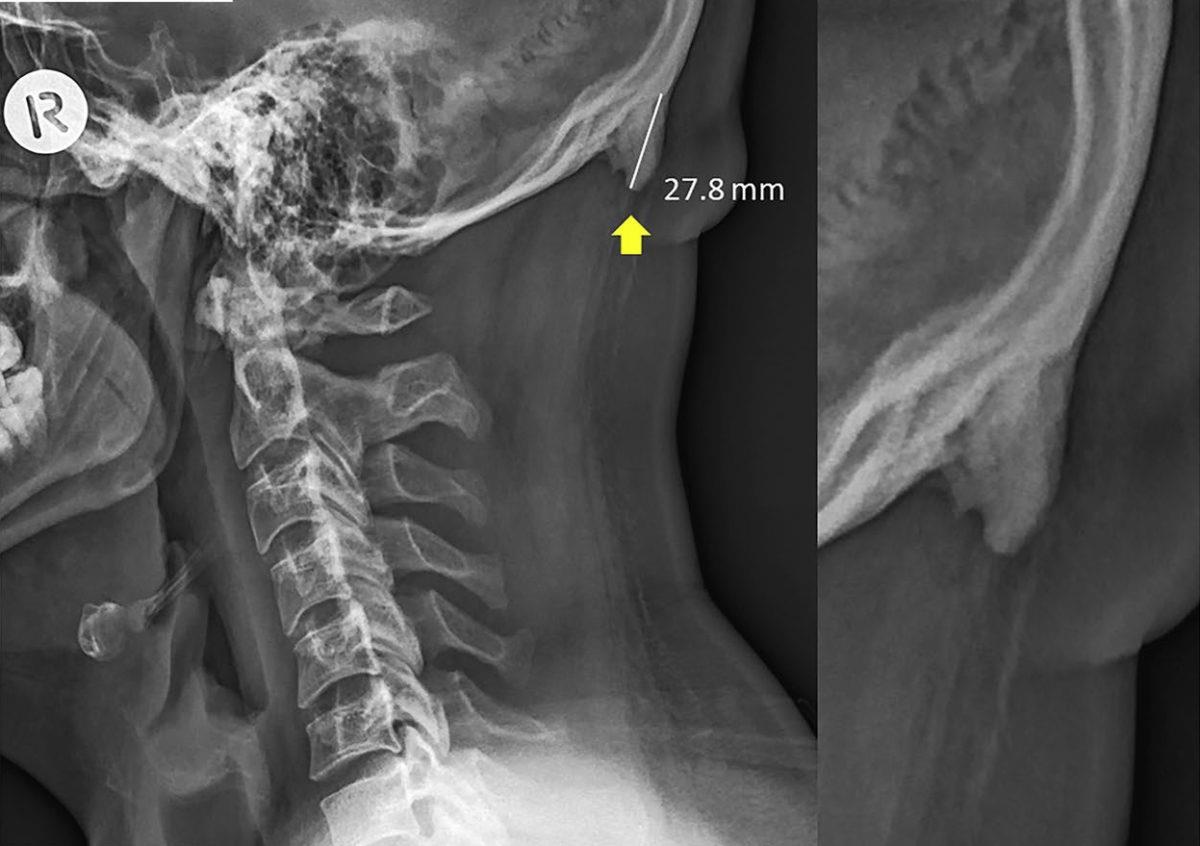

Đặc điểm mà Shahar nói đến giống như gai nhọn, nhô ra từ xương chẩm (là một xương sọ, phủ lên thùy chẩm của đại não), được tìm thấy ở phần dưới hộp sọ, ngay phía trên cổ. Nếu có nó, bạn có thể cảm nhận bằng ngón tay, ngay vị trí cột sống nối với đáy hộp sọ. Các nhà khoa học gọi đây là "gai nhô ngoài vùng chẩm" (external occipital protuberance).

![]() |

| Phần xương được gọi là "gai nhô ngoài vùng chẩm" (external occipital protuberance). Ảnh: Radiopaedia. |

Riêng Shahar và nhóm của mình, họ quyết định dấn sâu vào nghiên cứu . Ông cùng với học viên phân tích hơn cả nghìn hình chụp X-ray hộp sọ những người từ 18-86 tuổi. Họ đo lại bất kỳ mẫu xương nhọn nào và ghi nhận tư thế mỗi người tham gia.

Những gì các nhà khoa học tìm thấy thật bất ngờ. Phần xương phát triển này phổ biến hơn so với dự đoán, đặc biệt nhiều trên những người trẻ. Cứ một trên bốn người độ tuổi 18-30 lại có mẫu xương này.

Bạn có thể cảm nhận bằng ngón tay, ngay vị trí cột sống nối với đáy hộp sọ. Các nhà khoa học gọi đây là "gai nhô ngoài vùng chẩm" (external occipital protuberance), xuất hiện do thói quen sử dụng công nghệ.

Thật vậy, Shahar khá ngạc nhiên về kích cỡ những chiếc gai này. Trước đây, nghiên cứu gần nhất về vấn đề này được thực hiện tại một phòng thí nghiệm xương khớp ở Ấn Độ vào năm 2012.

Đó là phòng thí nghiệm chuyên về xương và họ có khá nhiều hộp sọ, nhưng bác sĩ ở đó chỉ tìm thấy một người có phần xương phát triển này. Nó vào khoảng 8mm, rất nhỏ, thậm chí còn không được Shahar đưa vào kết quả nghiên cứu. Còn vào 2019, chiếc xương đáng kể nhất có thể dài đến 30 mm.